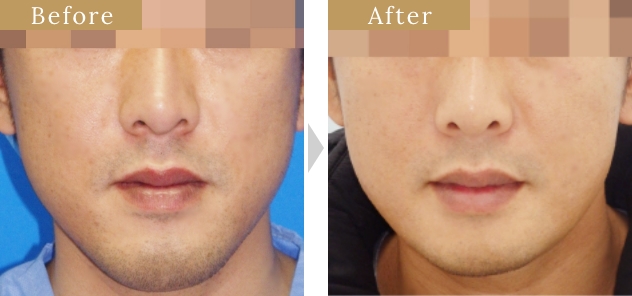

症例